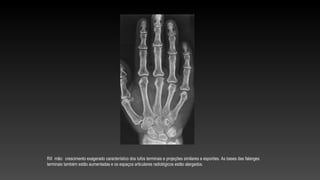

RX mão: crescimento exagerado característico dos tufos terminais e projeções similares a esporões. As bases das falanges

terminais também estão aumentadas e os espaços articulares radiológicos estão alargados.

RX mão: crescimentoexagerado característico dos tufos terminais e projeções similares a esporões. As bases das falanges terminais também estão aumentadas e os espaços articulares radiológicos estão alargados.